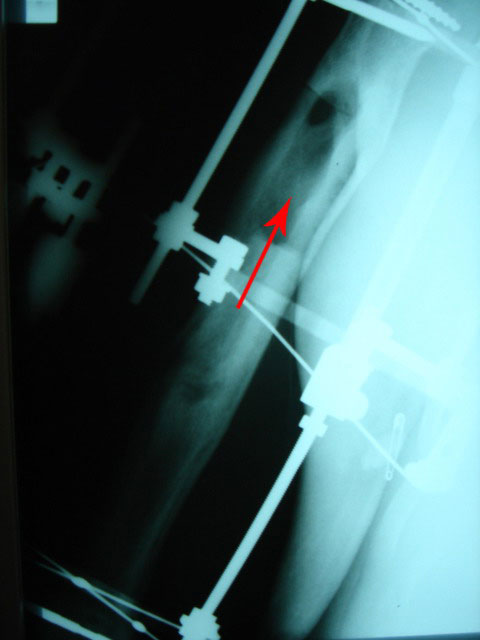

В том то и дело, что инфицирование остется. Я бы применил методику

возмещения инфициированной полости "скользящим отщепом" . Как говорил

Илизаров "инфекция сгорает в огне регенерации" Поэтично, но поверьте это

работает почти безотказно, если конечно больной согласится на очередной

аппарат

Снимки в приложении, удачи

Аршак Мирзоян

Ереванский Центр Реконструкции и

Удлинения Конечностей